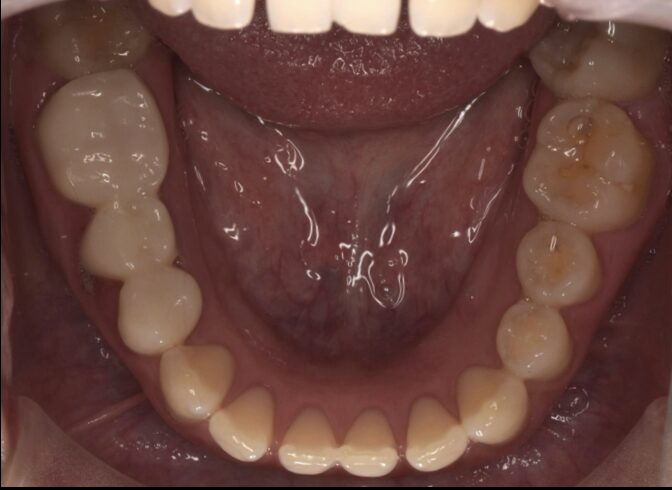

ポンティック下の残根を除去しインプラント治療した症例

Before